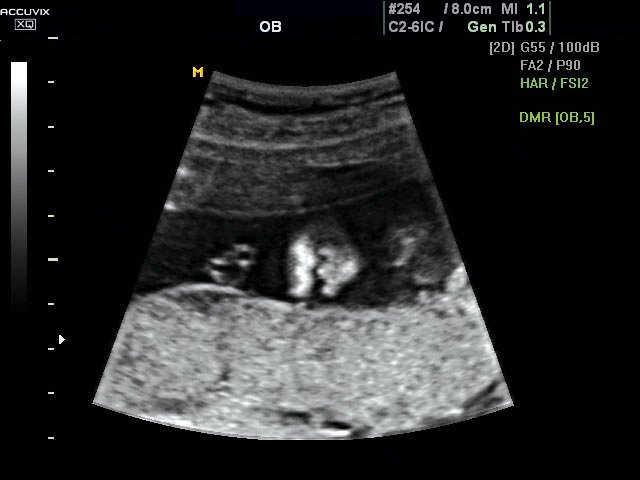

Брюшная полость плода в продольной плоскости, 2D (без Dynamic MR™).

Брюшная полость плода в продольной плоскости, 2D (в режиме Dynamic MR™).